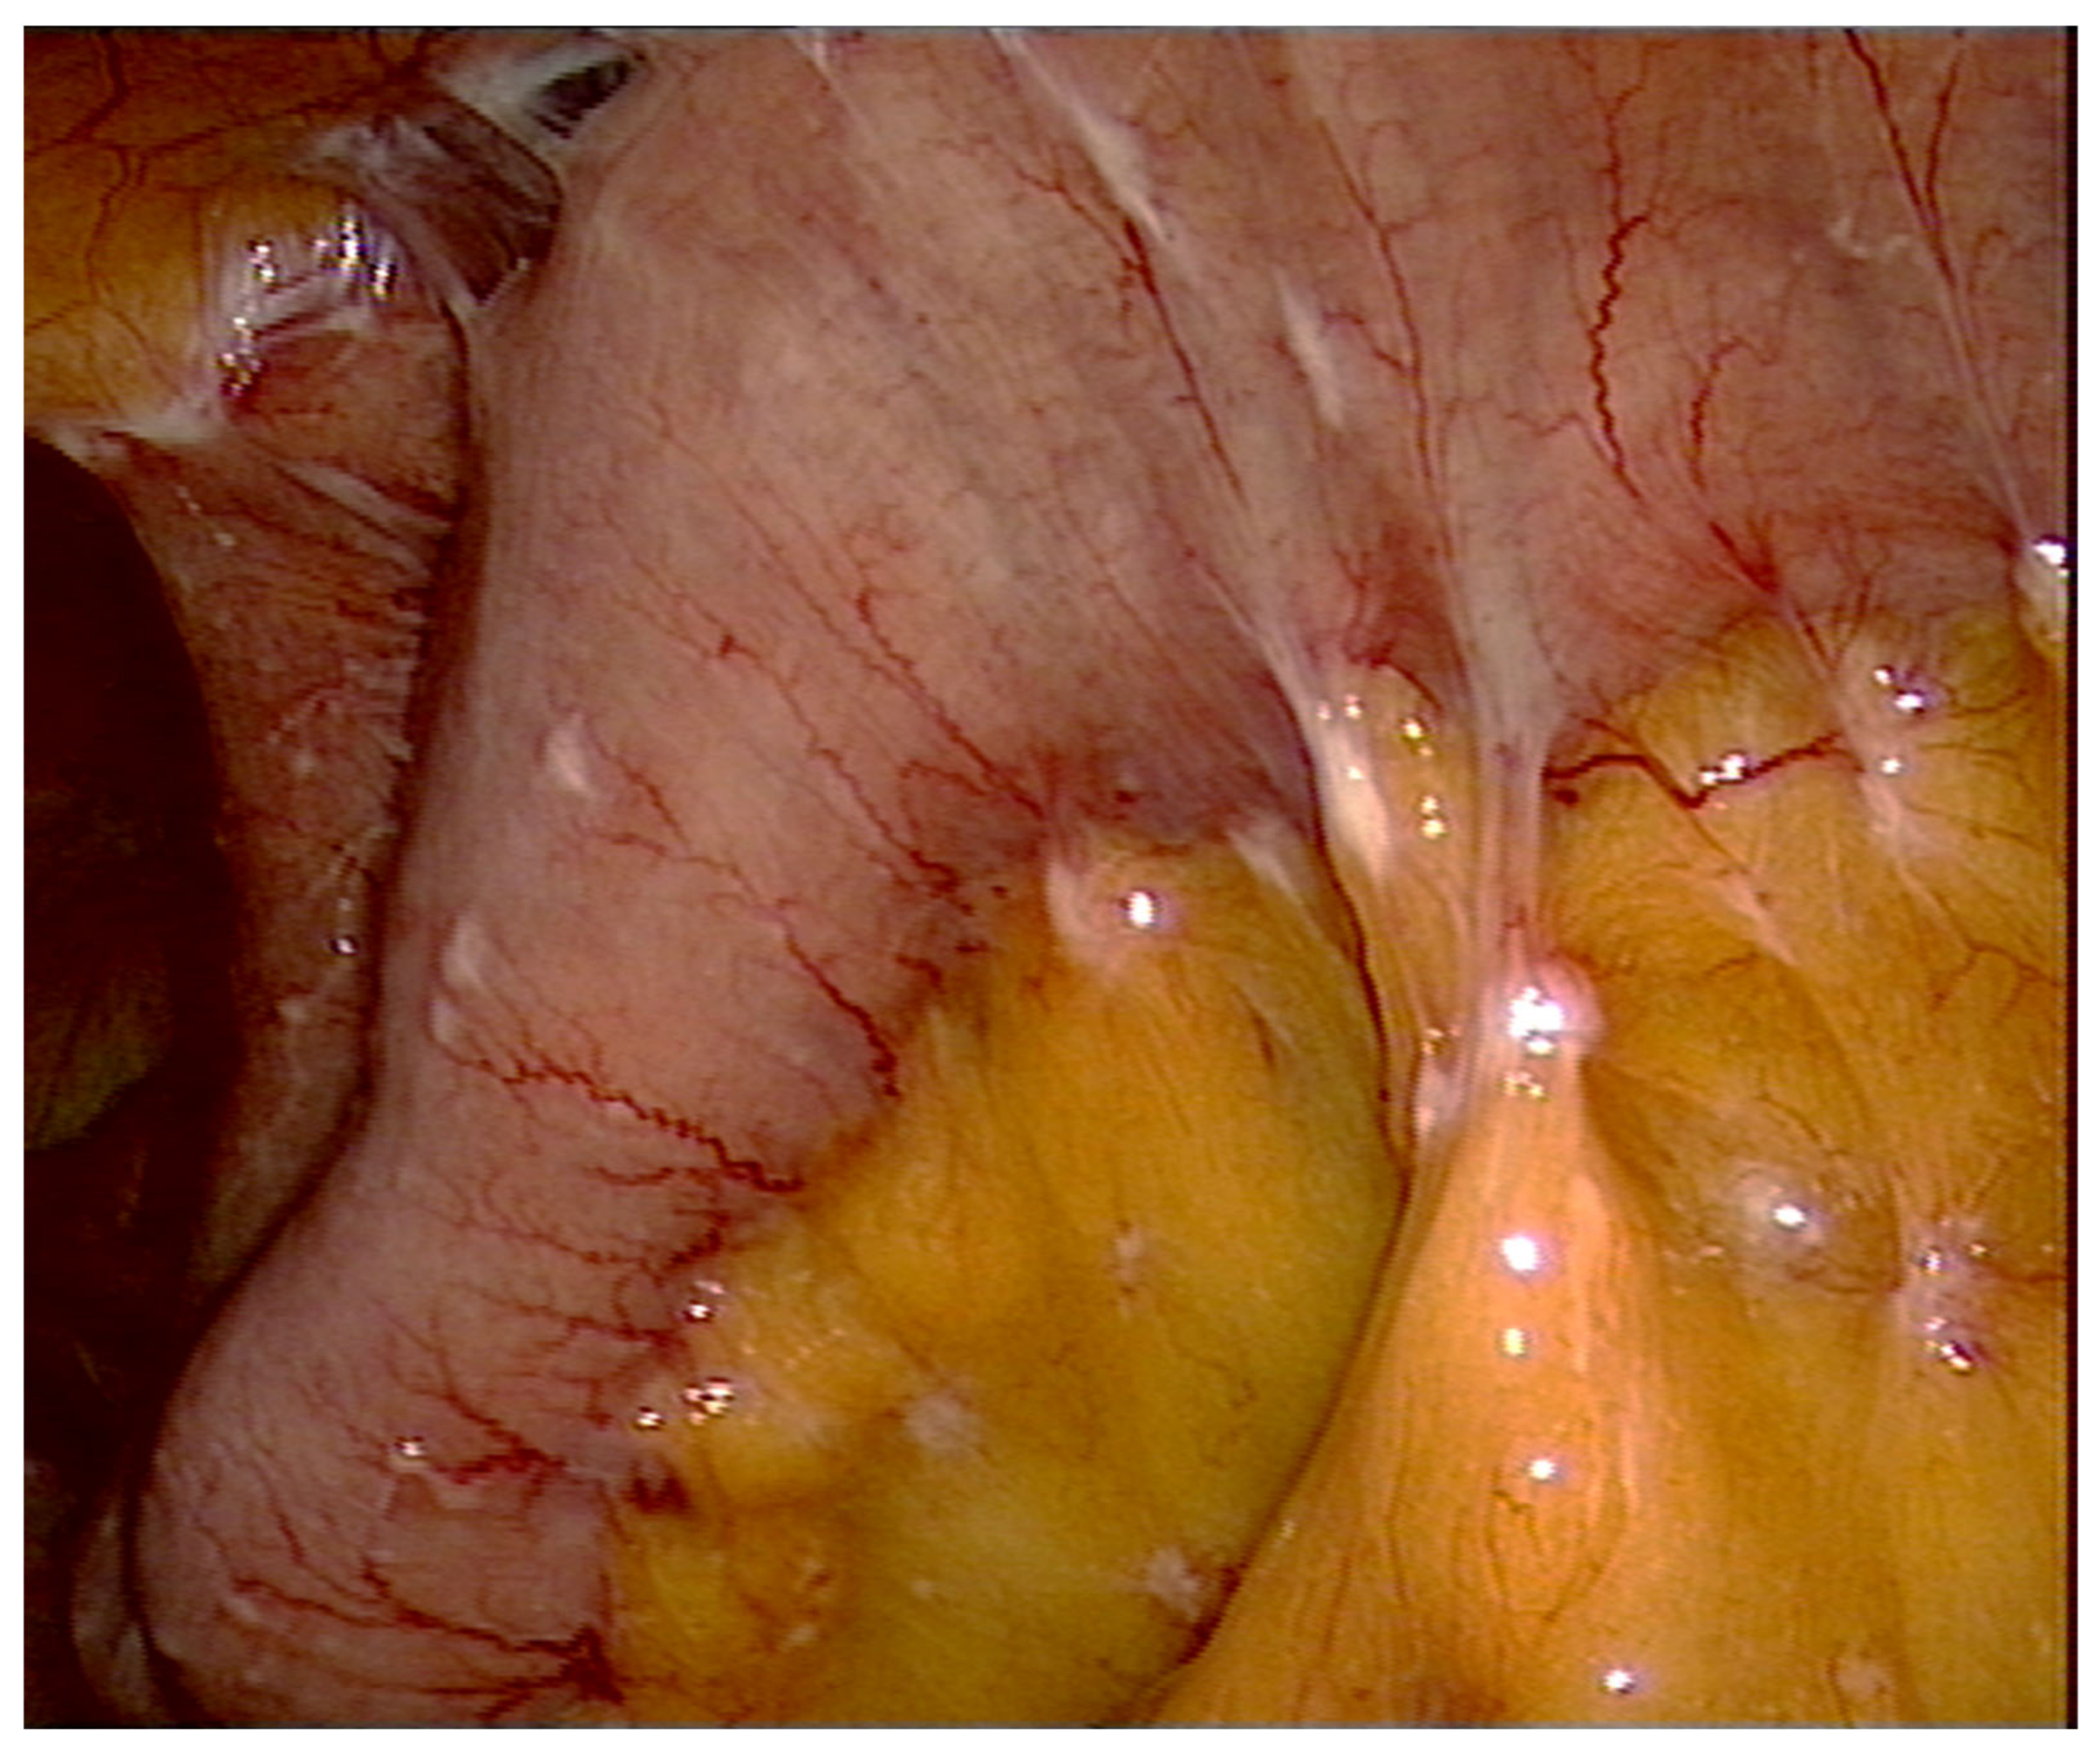

2. How to Explore?